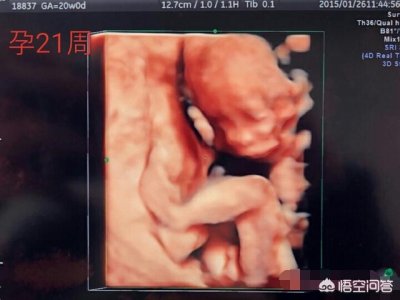

想与男朋友分手的最快捷方法,就是告诉他你爱他,你要为他生一个孩子,他的反应多半是逃得无影无踪。